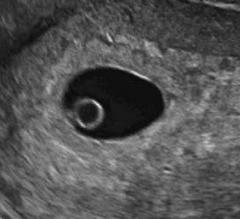

Το υπερηχογράφημα αποτελεί τον ακρογωνιαίο λίθο κατά την εκτίμηση της κατάστασης στο πρώτο τρίμηνο της εγκυμοσύνης.

- Θα απεικονίσει τη θέση του εμβρυικού σάκκου και επιβεβαιώσει την ύπαρξη ενδομητρίου κυήσεως ή θα θέσει την υποψία ή ακόμα και τη διάγνωση εξωμητρίου κυήσεως. Να επισημάνουμε ότι σε τιμές βhCG >1000iu θα πρέπει να βλέπουμε υπερηχογραφικά ενδομήτριο σάκκο κύησης. Σε αντίθετη περίπτωση πρόκειται για εξωμήτριο κύηση ή πλήρη αποβολή, που έχει προηγηθεί.

- Η διαπίστωση εμβρυικής καρδιακής λειτουργίας θα επιβεβαιώσει τη βιωσιμότητα της κύησης και θα πρέπει να επισημάνουμε ότι η καρδιακή λειτουργία εμφανίζεται συνήθως στην αρχή της 7ης εβδομάδας και σε CRL >2.5mm.

- Κατά την αρχόμενη κύηση στην 5η εβδομάδα όταν αυτή δεν απεικονίζεται ακόμη υπερηχογραφικά τα ευρήματα αξιολογούνται σύμφωνα με τα επίπεδα της β-χοριακής (β-hCG) στο αίμα της επιτόκου και η εκτίμηση της βιωσιμότητας βασίζεται στο φυσιολογικό ρυθμό αύξησης της βhCG.